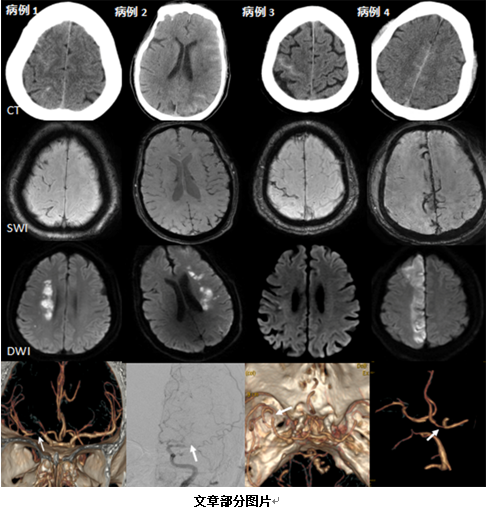

最終在1023例蛛網(wǎng)膜下腔出血患者中發(fā)現(xiàn)符合自發(fā)性凸面蛛網(wǎng)膜下腔出血患者15例(發(fā)生率為1.46%),同時(shí)合并急性腦梗死的9例,發(fā)生率僅為0.87%。這跟國(guó)外的研究相接近。進(jìn)一步分析得出這類疾病重要的結(jié)論:比如常發(fā)生在梗死后2d。其中,顱內(nèi)動(dòng)脈狹窄或閉塞可能是這類疾病的主要病因。最常出血的部位為頂葉;治療上積極的抗栓和(或)支架治療并未增加出血風(fēng)險(xiǎn),且預(yù)后良好。該文提供了我國(guó)這類疾病的寶貴的臨床數(shù)據(jù)。文章很好的回答了該少見(jiàn)臨床現(xiàn)象的發(fā)生率、發(fā)生時(shí)間、發(fā)生部位及治療經(jīng)驗(yàn)等關(guān)鍵性問(wèn)題,得出的臨床結(jié)論對(duì)臨床醫(yī)師具有重要參考作用。